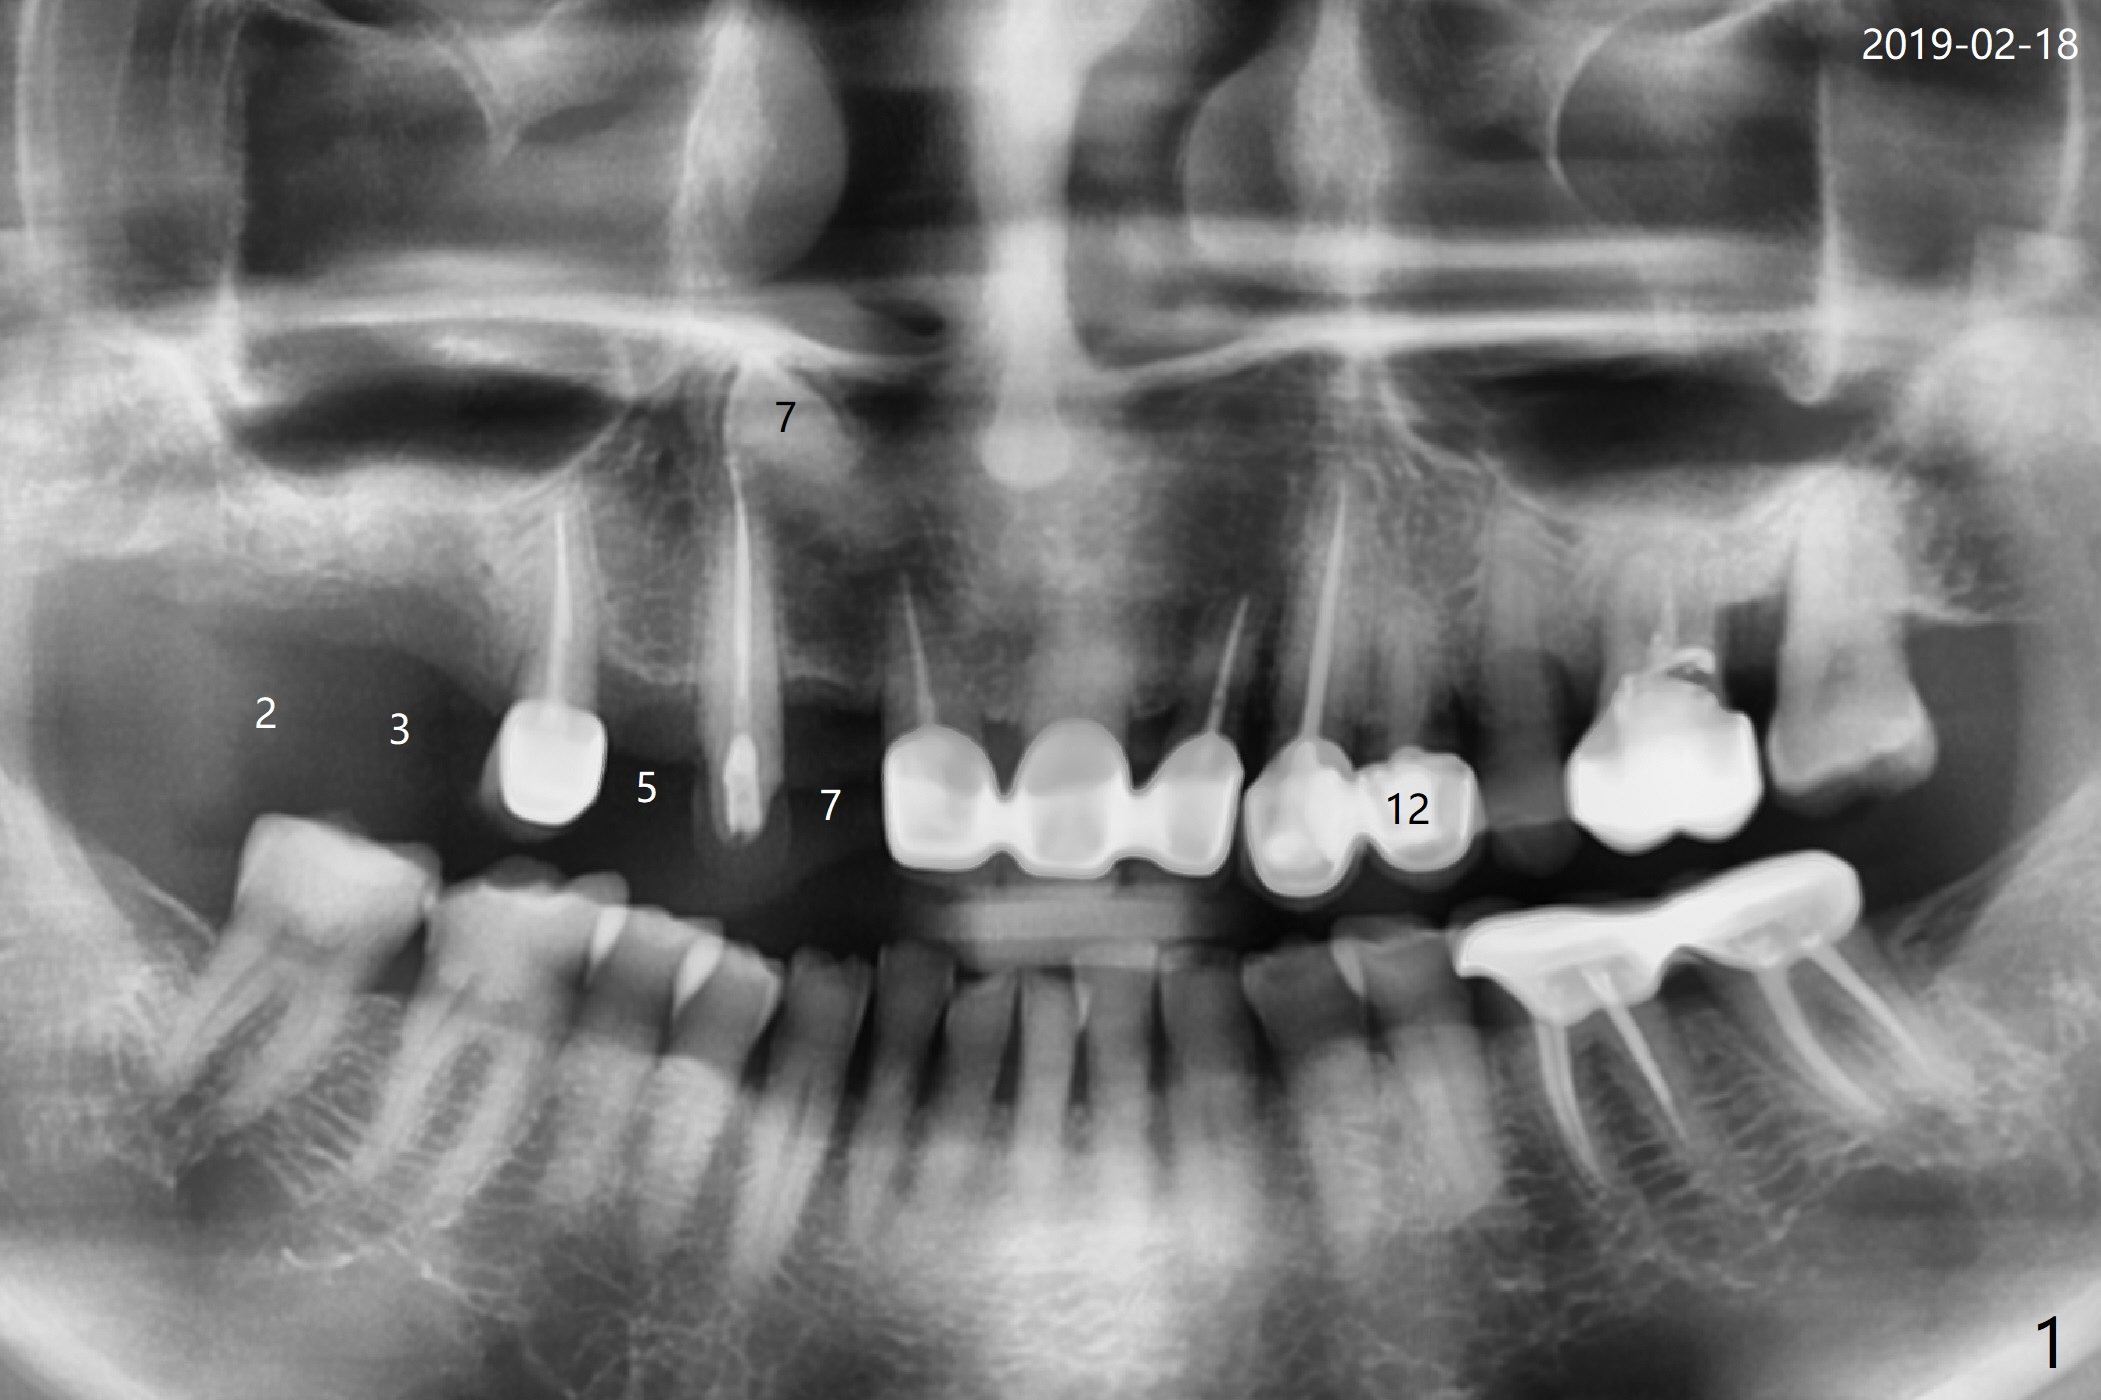

68岁女右上4个植牙后(图一),左上4(12号牙)根尖周围炎,根管闭锁(图二),牙周袋9毫米。切割3,4连冠,拔除4,为了减少腭侧骨板吸收,植体也不要植入太腭侧(图三,四)。其实顺腭侧根钻洞偏近中,很难纠正,最后位点保存